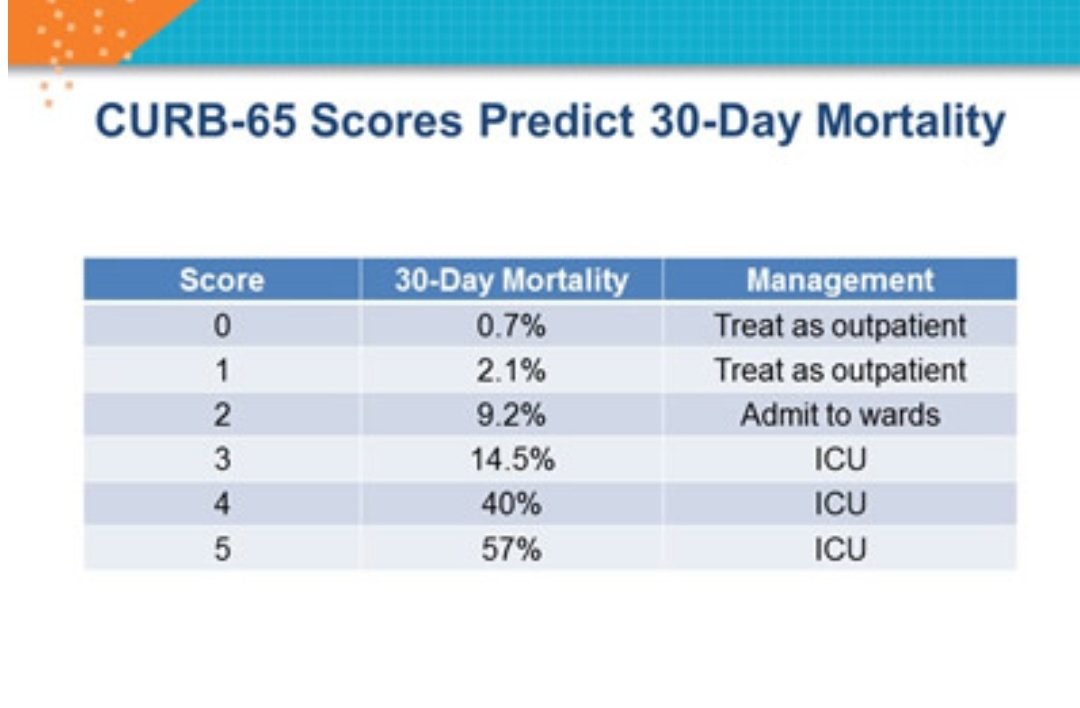

في نظام نقاط CURB65 بحسب درجة الخطورة،

ودي اختصار للتالي:

C

Confusion

عدم الوعي

U

Urea => 7 mol/l

نسبة البولينا في الدم

R

Respiratory rate => 30/min

عدد مرات التنفس في الدقيقة

B

Blood pressure

ضغط انقباضي أقل من ٩٠

أو انبساطي أقل من ٦٠

65

Age => 65

العمر ٦٥ أو أكثر